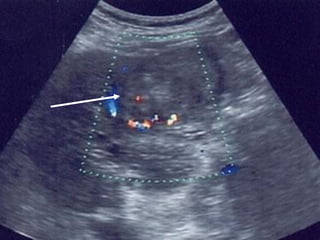

■Siªu ©m bông:

+Khèi u: ↓ ©m, ↑ ©m, hçn hîp ©m, quÇng halo

+X©m lÊn TM cöa, TM trªn gan

+D·n ®êng mËt trong gan ë phÝa trªn khèi u